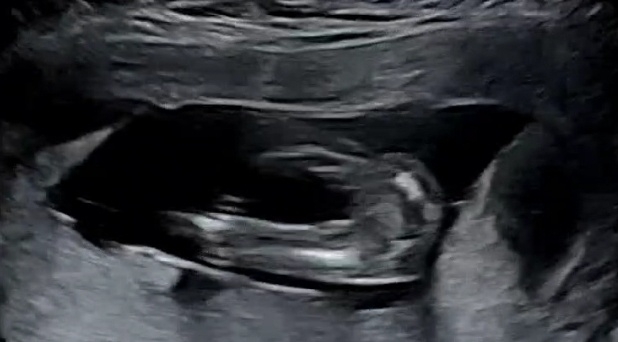

성별 문의드려요 ㅎㅎ

14주 1일차에 초음파로봤을땐 딸인것같다고 말씀해주시긴했는데 딸이었다가 아들로 변하는 반전있던분들 계신가요?? 확정이면 좋겠는데 아직 확정짓긴 어렵다고하더라구요 '-'